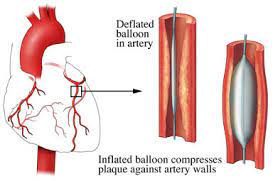

Value added benefits of the Coronary Angioplasty:

Value added benefits of the Angioplasty PTCA :

Value added benefits of the Percutaneous transluminal coronary angioplasty (PTCA):